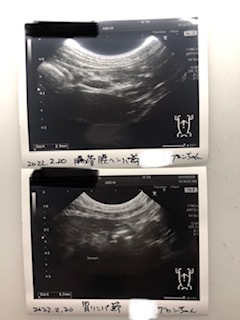

エコー検査

特に問題なし